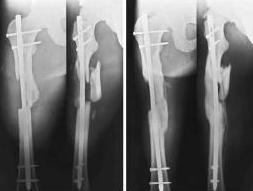

Здравствуйте , уважаемые коллеги. Обратился пациент, мужчина 42лет. для дальнейшего

лечения. Травма 11.09., ДТП.

15.09 проведено оперативное лечение (Блокирующий стержень левого

бедра - статическая система. Открытое вправление вывиха в суставе

Лисфранка и фиксация мет. фиксаторами.)

1. По бедру... Стержень конечно тонковат, торчит в колено..не совсем ясно, что там с прокстимальным блоком(... Если не будет нагрузки, получите замедленное стащение, потом когда датите нагрузку получите перелом винтов (в лучшем случае), штифта - в худшем(

То, что перелом распространяется на сустав не имеет никакого значения и влияния (в данном конкретном примере) для отсрочки динамизации и нагрузки.

2- При такой Ro - картине будет ложный сустав или рефрактура после

удаления стержня, и поэтому идти на пластину с костной пластикой.

Сорри, коллега, эту фразу я ваще не понял... Сомневаетесь в перспективах сращения? что ж, вполне обоснованно! Просто перештифтуйте ЗАКРЫТО более массивным штифтом, с рассверливанием и заблокируйте динамично..